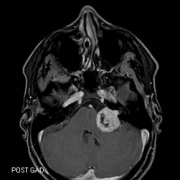

当耳鸣患者去耳鼻喉科寻求帮助时,诊断的一步通常是听力学检查和核磁共振成像(MRI)。磁共振检查是为了排除听觉神经瘤或其他器质性耳鸣的可能性...